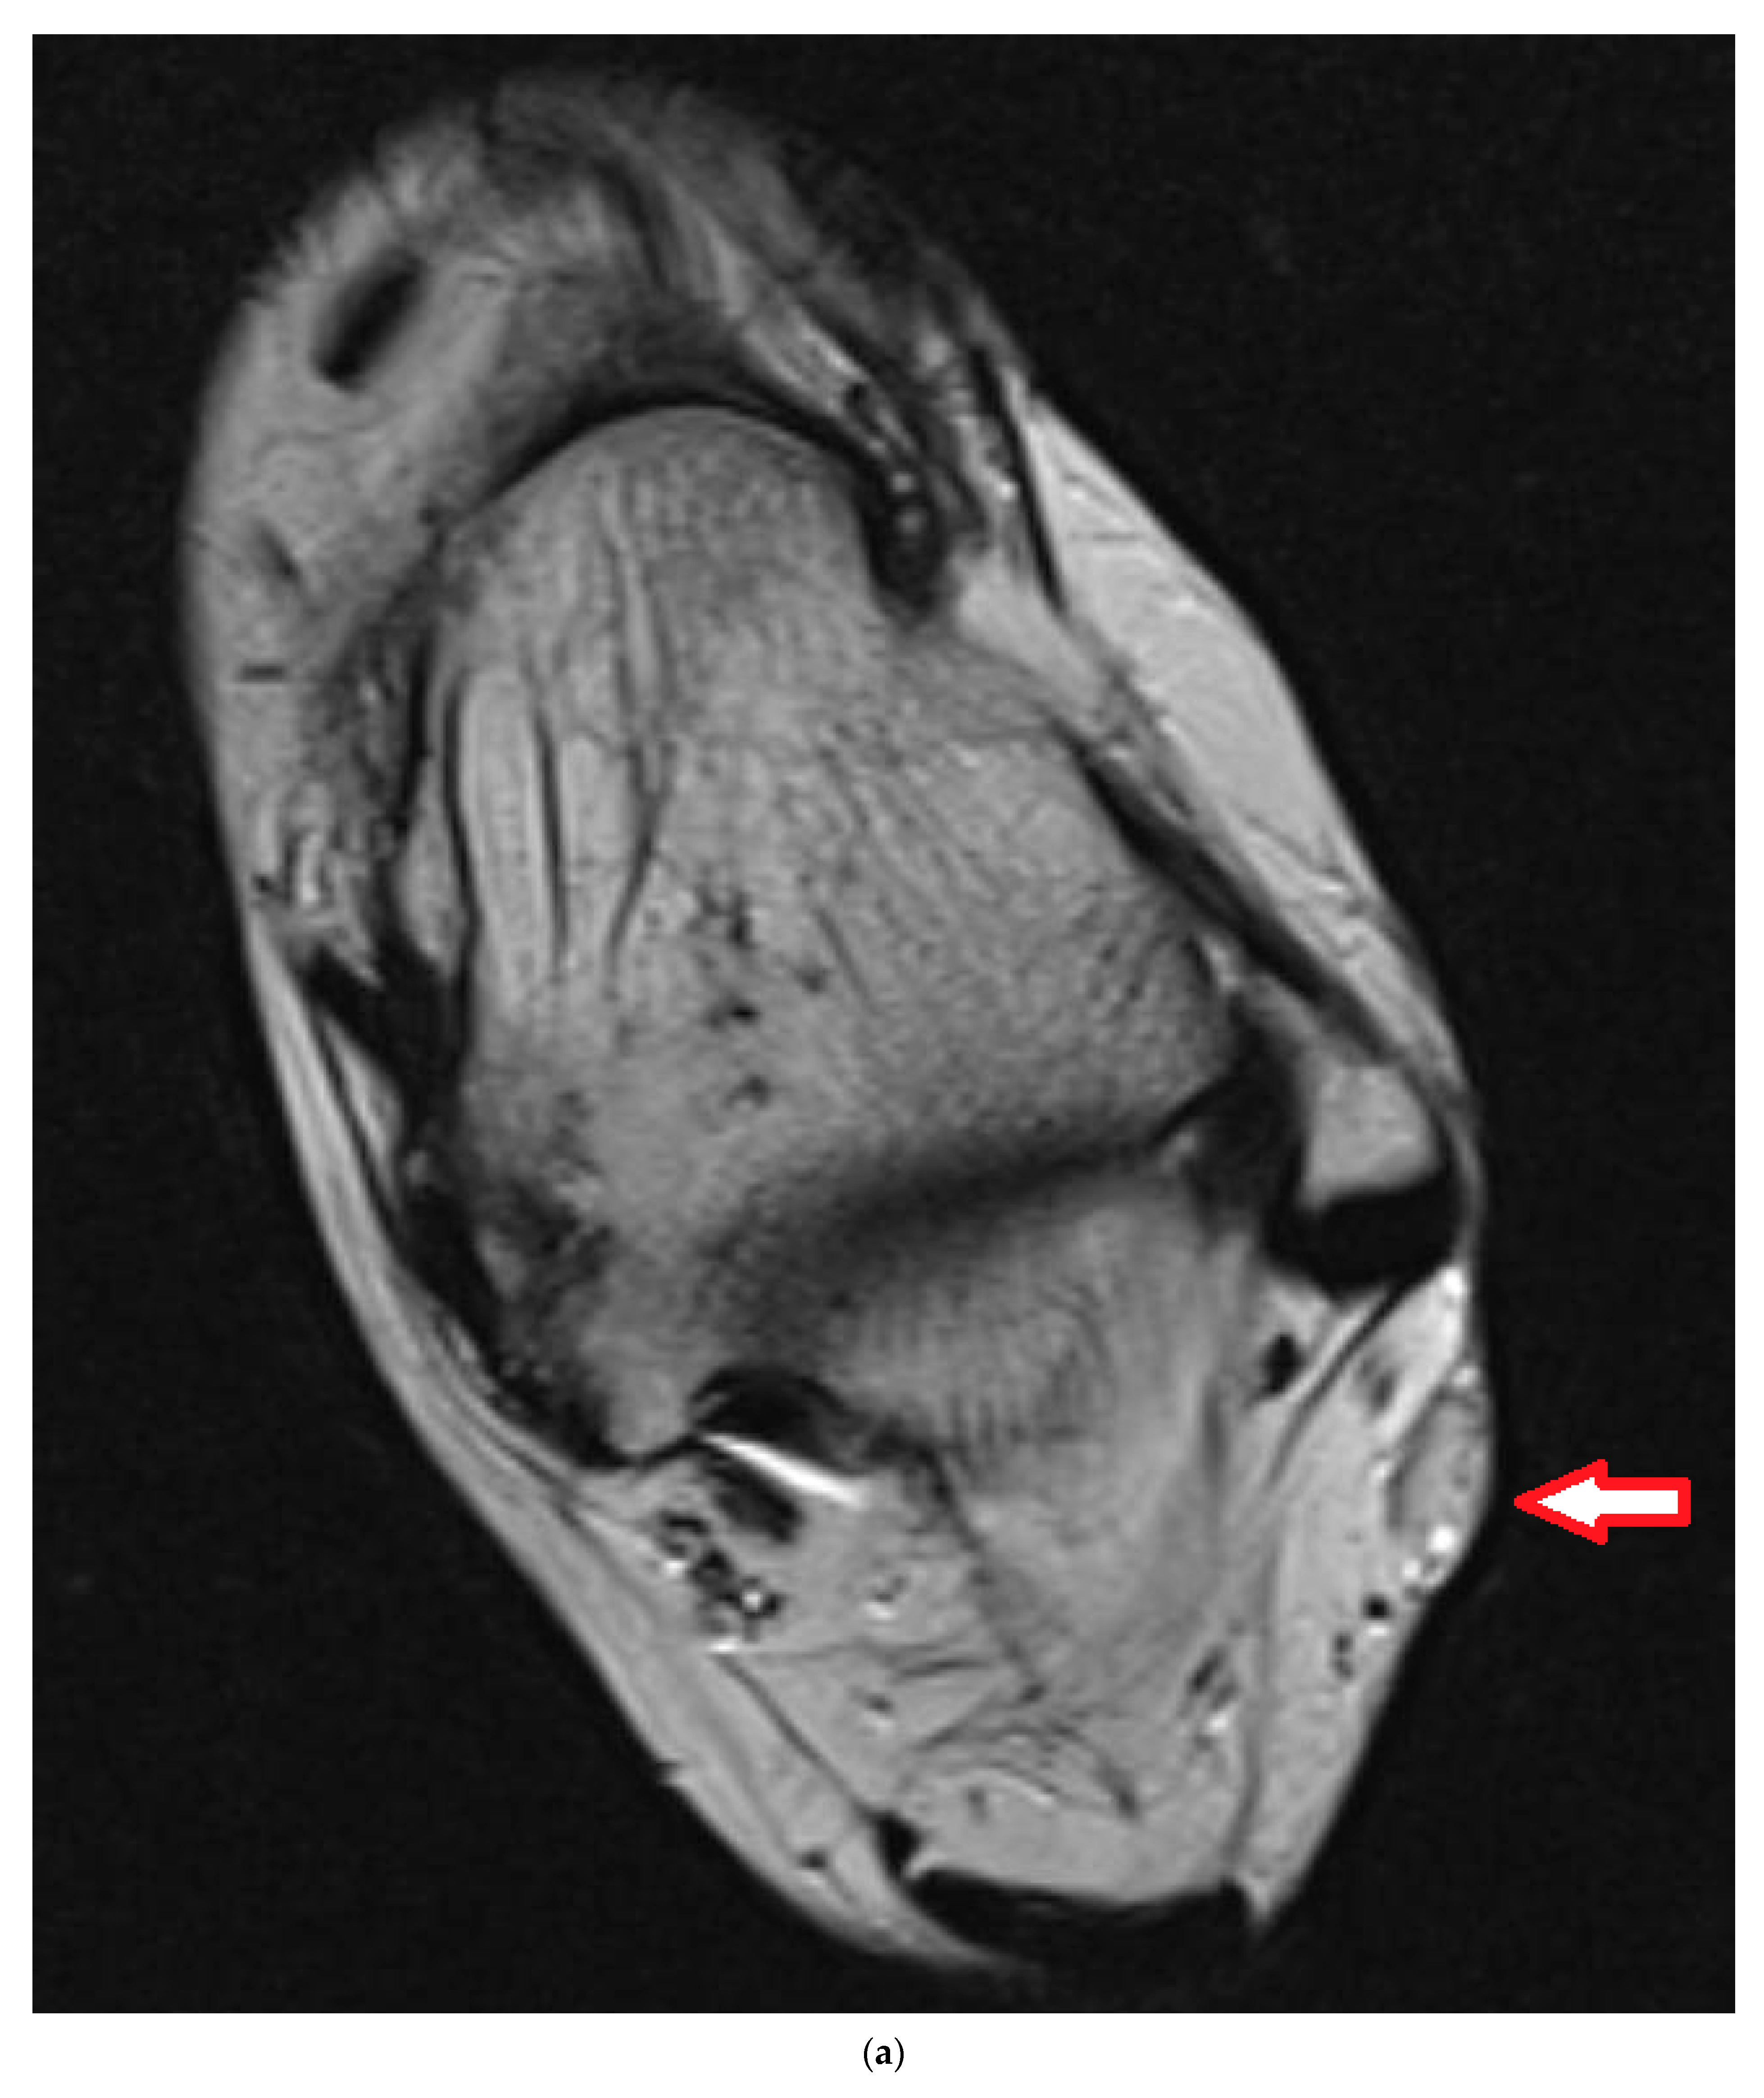

4. Illustrating Case